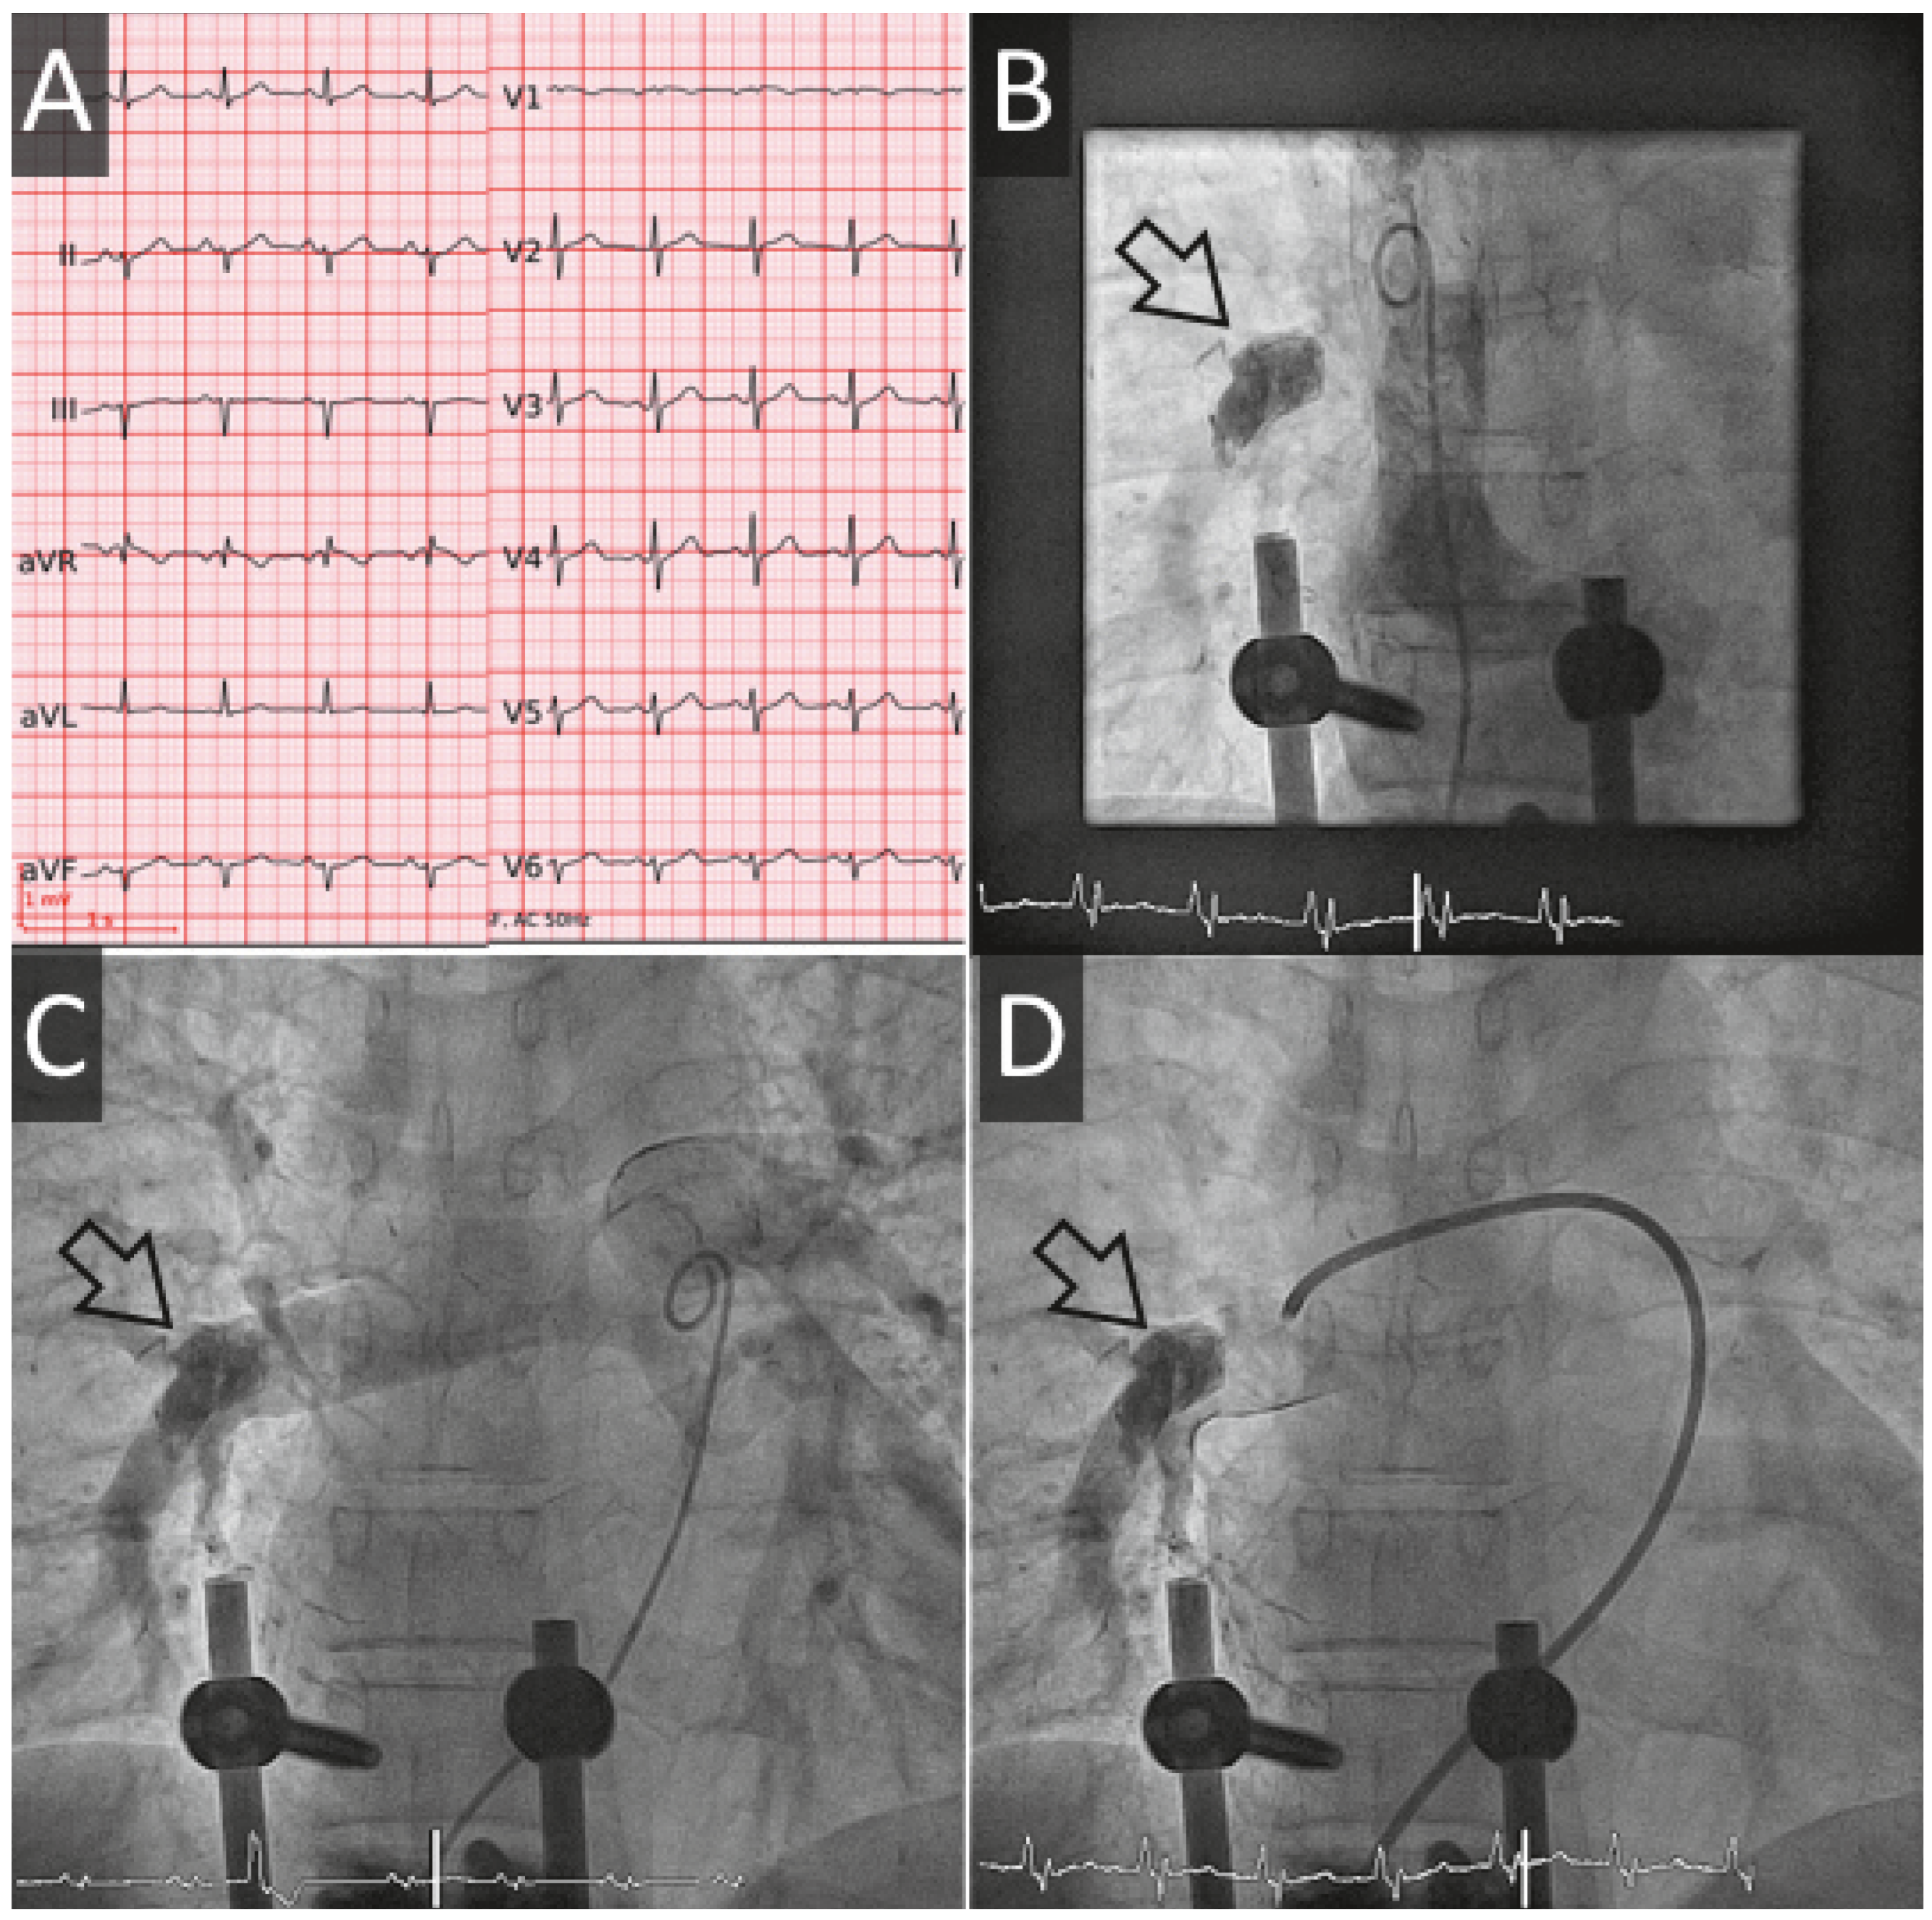

Figure 3. Cas #3. Panel A. Echocardiographie transthoracique révèle un filament de ciment (flèches blanches creuses) attaché à l’oreillette droite. Panel B. Des emboles périphériques sont visibles sur la radiographie de thorax. Panel C. Un CT thoracique confirme l’image échocardiographie (en bas à droite), mais révèle plusieurs autres fragments non clairement visualisés à l’échocardiographie.

Un patient de 72 ans, connu pour une maladie coronarienne monotronculaire (IVA moyenne), une sténose aortique modérée et un syndrome myélodysplasique, bénéficie de 2 vertébroplasties lombaires (L4, puis L3) dans le courant de l’été 2016. A l’issue de ces interventions, il développe une dyspnée stade NYHA IV mise sur le compte d’une embolisation pulmonaire de ciment qui sera confirmée par un angio-CT. Une échocardiographie exclut une hypertension artérielle pulmonaire et démontre une embolisation intracardiaque. Au vu de la taille des emboles et de l’absence d’hypertension artérielle pulmonaire, une attitude conservatrice est décidée et le bilan est complété par un CT-cardiaque. Ce dernier examen révèle la présence de multiples spicules millimétriques (5 au niveau duventricule droit et 1 au niveau de l’oreillette droite) et en périphérie des artères pulmonaires droites. Au vu de la taille et de la quantité de filaments chez un patient asymptomatique, l’attitude conservatrice est maintenue. Un suivi échocardiographique est effectué à 6 mois. L’évolution de la dyspnée est favorable, avec un stade NYHA II, 9 mois après l’embolisation.